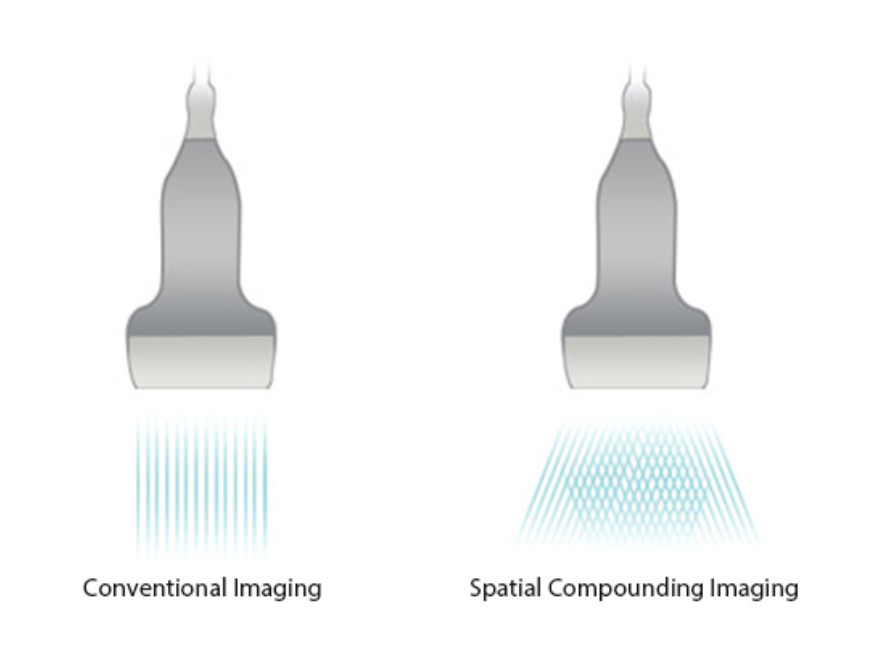

iBeam?

Permits use of multiple scanned angles to form a single image, resulting in enhanced contrast resolution and improved visualization